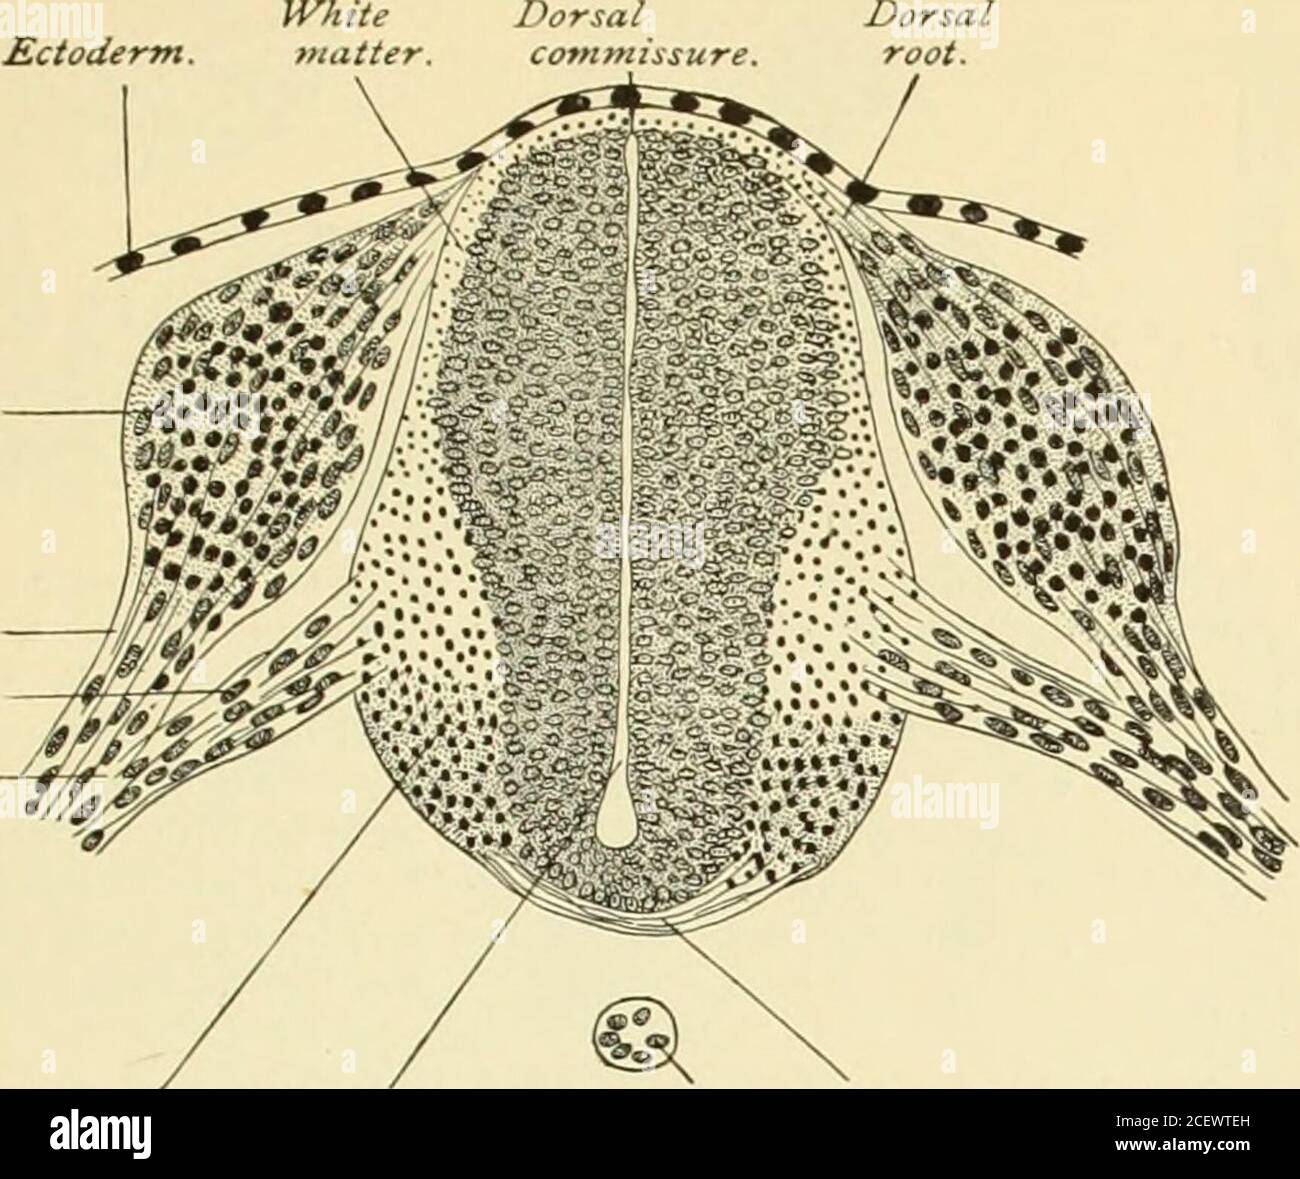

RM2CEWTEH–. Ein amerikanisches Textbuch der Geburtshilfe. Für Praktizierende und Studenten. il. Zirbelkörper:posteriore com-misure : ve-lum interpos-ituiu. Optische Thalami. Dritter ven-tricle. II. Mittlere Primärhirn-Vesikel. Mittelhirn. Zerebrale Pedun-cles : poste-rior perforierte Lamina. Korpora Quad-Rigemina. Genikulatkörper;Brachia. Aquädukt von Syl-vius. B. III.posteriorer Primärbereich 4. Hinterhirn. Pons Varolii. Anteriores Velum med-ullary:cerebellum : posteriores Velum med-ullary. Superior andMiddle pe-Dunkles des Kleinhirns. Fourthventri-cle. Gehirn-Stiel. Gehirn-Vesikel. 5. Nach-Gehirn. Medulla oblon-gata. Dünne Abdeckung von po